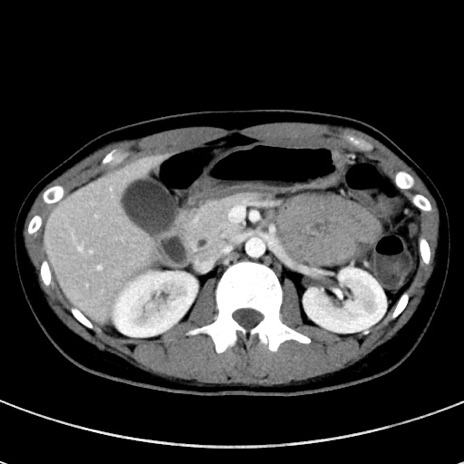

症例17(横断像)

【症例】20歳代女性

【主訴】嘔吐、下腹部痛

【現病歴】昨日夕食後に嘔吐し下腹部痛が出現。本日になっても嘔吐持続し改善しないため来院。

【身体所見】意識清明、BT 37.2℃、BP 108/67mmHg、腹部:平坦、やや硬、下腹部正中から右にかけて圧痛あり、反跳痛軽度あり、tapping pain(+)。

【データ】WBC 13600、CRP 14.94